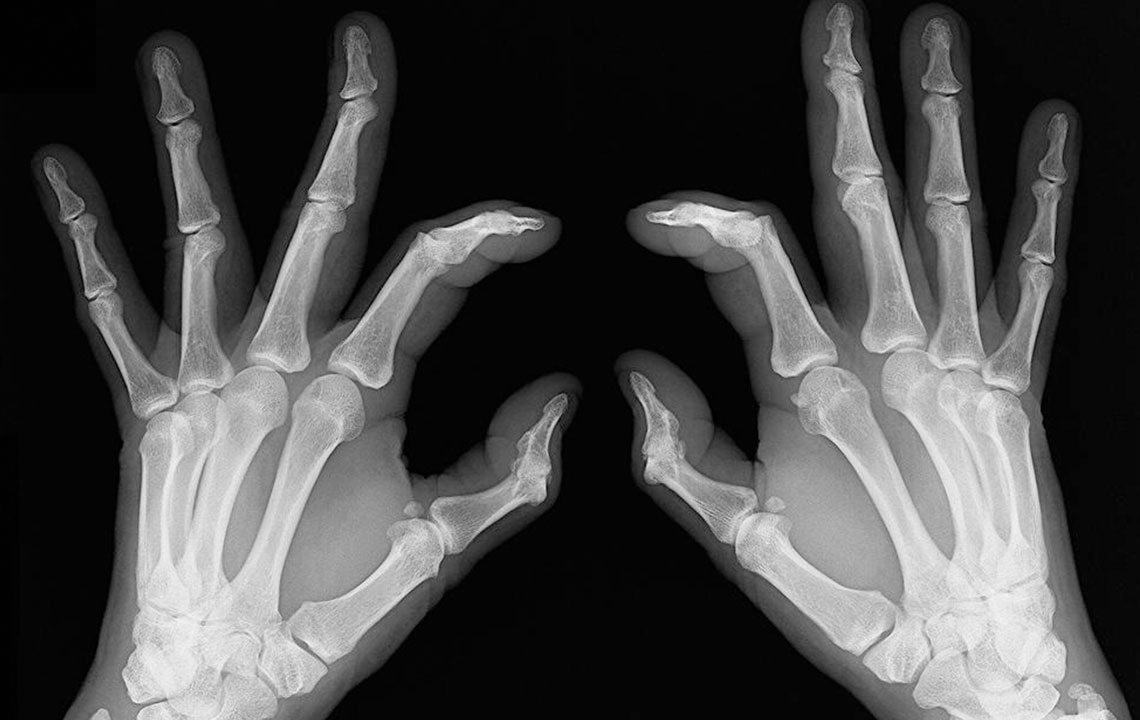

People who have rheumatoid arthritis often wake-up early in the morning complaining of stiff joints and restricted movement. The mobility is back slowly and with little joint movements . Joint redness: Sometimes the troubled area also experiences redness and feels warm to the touch. However, make sure the redness is not due to reasons such as a bruise or a scrape of the skin. Bone deformation: Arthritis also attacks the bones and makes them crooked and stiff. Look out for signs of any subtle changes in your joints and test them for pain levels.